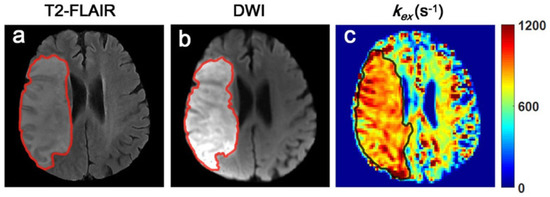

- Wang, Z.; Shaghaghi, M.; Zhang, S.; Zhang, G.; Zhou, Y.; Wu, D.; Zhang, Z.; Zhu, W.; Cai, K. Novel proton exchange rate MRI presents unique contrast in brains of ischemic stroke patients. J. Neurosci. Methods. 2020, 346, 108926. [Google Scholar] [CrossRef]